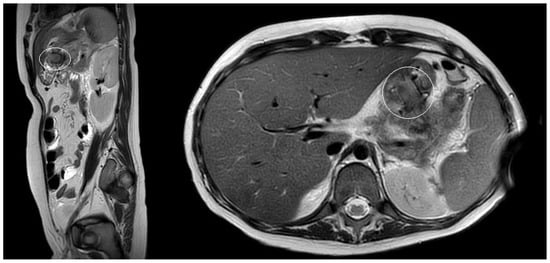

Patient 1: A 15-year girl underwent elective surgery for a pancreatic solid pseudopapillary neoplasm: we performed a laparoscopic partial distal pancreatectomy with saving of the distal part of the pancreatic tail, that was not infiltrated by neoplasm. Few days after surgery, she developed a pancreatic leak with acute pancreatitis, with subsequent evidence of pancreatic pseudocyst. At preoperative MRI the pseudocyst had a major diameter of 10 cm (Figure 3). She initially underwent a first attempt of laparoscopic surgical debridement with placement of 2 tubular drains. As the patient still presented abdominal pain and vomit, US was performed, demonstrating an increase of the volume of the pseudocyst. After 8 days from the surgical procedure, the patient underwent EUS-guided cystogastrostomy and EC-LAMS placement as a rescue procedure. Post-operative course was uneventful and routine US performed after cystogastrostomy, showed a progressive resolution of the collection; retrogastric collection was no more detected 19 days after the procedure, suggesting its complete resolution. Twenty-one days after EC-LAMS positioning, we performed an endoscopy to remove the device; no complications occurred during or after the procedure.

Figure 3.

Patient n°1 MRI. Pseudocyst in the omental bursa with maximum diameter 10 cm.